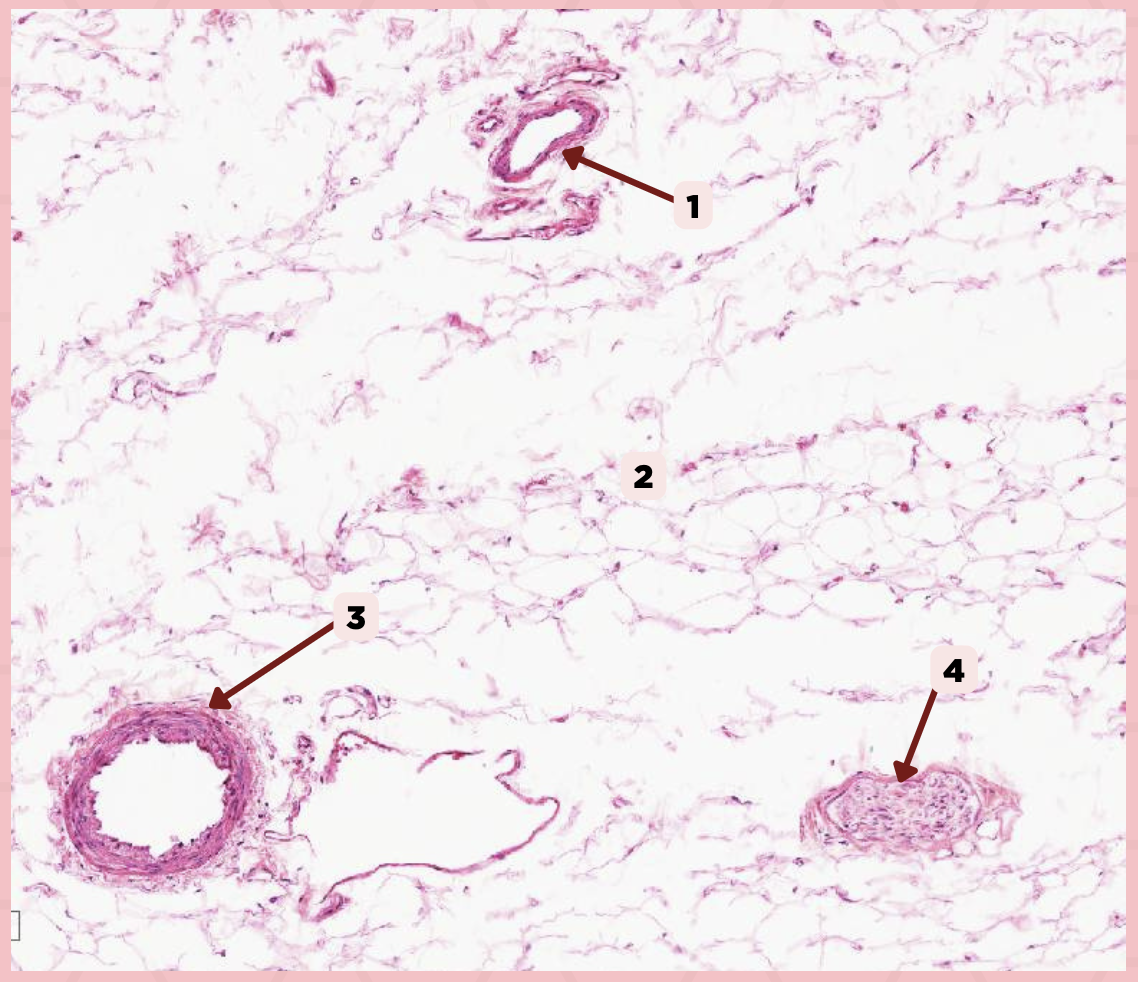

Cheek

Identify the specimen.

Vein

Identify the structure labeled as 1.

Hypodermis

Identify the structure labeled as 2.

Artery

Identify the structure labeled as 3.

Nerve

Identify the structure labeled as 4.